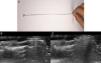

Descripción de la técnicaUna mujer de 43 años, intervenida previamente de un tumor glómico subungueal en el cuarto dedo de la mano derecha mediante la misma técnica que posteriormente se detalla, pero sin control ecográfico preoperatorio, acudió a consultas por dolor paroxístico intenso. La exploración clínica fue normal, sin evidencia de recidiva de tumor glómico subungueal (fig. 1A). Se realizó una ecografía cutánea con sonda de 18Mhz con diagnóstico de recidiva del tumor en el lecho ungueal de 3,1mm de tamaño (fig. 1B). Previo a la cirugía se localizó ecográficamente el tumor y se realizó marcaje de la lámina ungueal utilizando una guía de fabricación «casera» (fig. 2A) Para ello se mantuvo la sonda ecográfica longitudinal al aparato ungueal e introducimos la guía ecográfica perpendicular a la sonda produciéndose una reverberación en cola de cometa que nos ocultará el tumor (fig. 2B). En este punto, mantenemos la guía ecográfica fija, retiramos la sonda y realizamos el marcaje de la lámina ungueal (fig. 2C).